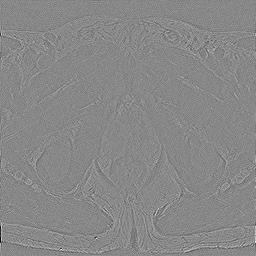

Modern deep neural networks struggle to transfer knowledge and generalize across diverse domains when deployed to real-world applications. Currently, domain generalization (DG) is introduced to learn a universal representation from multiple domains to improve the network generalization ability on unseen domains. However, previous DG methods only focus on the data-level consistency scheme without considering the synergistic regularization among different consistency schemes. In this paper, we present a novel Hierarchical Consistency framework for Domain Generalization (HCDG) by integrating Extrinsic Consistency and Intrinsic Consistency synergistically. Particularly, for the Extrinsic Consistency, we leverage the knowledge across multiple source domains to enforce data-level consistency. To better enhance such consistency, we design a novel Amplitude Gaussian-mixing strategy into Fourier-based data augmentation called DomainUp. For the Intrinsic Consistency, we perform task-level consistency for the same instance under the dual-task scenario. We evaluate the proposed HCDG framework on two medical image segmentation tasks, i.e., optic cup/disc segmentation on fundus images and prostate MRI segmentation. Extensive experimental results manifest the effectiveness and versatility of our HCDG framework.